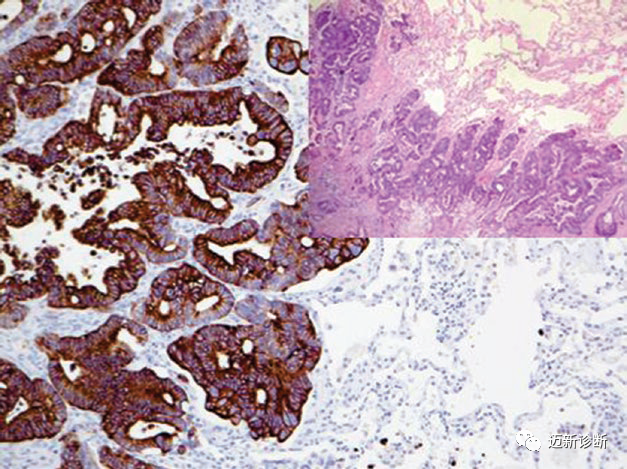

图2. 胸腔积液标本中,间皮瘤细胞,CK5阳性。

图4. 转移性结直肠腺癌,CK20强阳性表达。